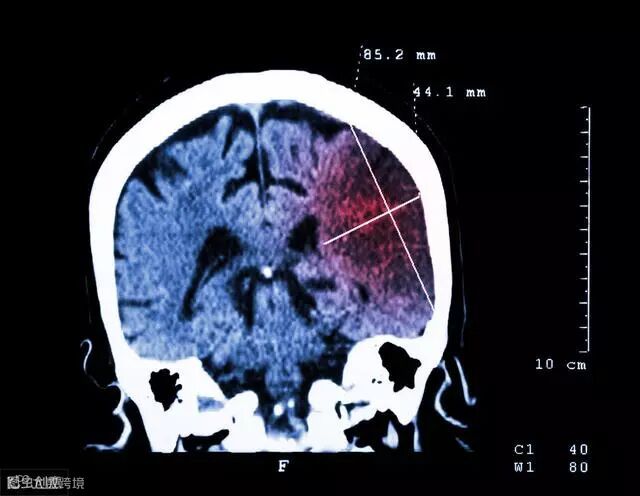

是脑卒中最强的独立危险因素,该时段脑卒中的发生率是其他时段的3~4倍;